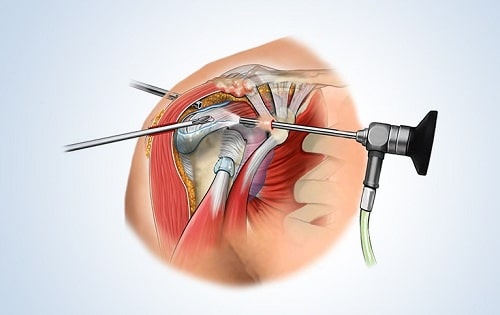

- بهترین روش برای تشخیص پارگی لابروم آرتروسکوپی شانه است. متأسفانه این یک روش عملی است و به نوعی بیهوشی نیاز دارد.

- رسیدن به تشخیص نیز در بخشی از جراحی نیاز به تجربه دارد، زیرا آناتومی داخل شانه میتواند بسیار پیچیده باشد.

پارگی ناشی از بی ثباتی یا تحریک و یا جابجایی شانه ، نیاز به اتصال لابروم به لبه حفره دارد که میتوان با برش در جلوی شانه این اتصال را انجام داد. یا میتوان با تکنیکهای آرتروسکوپی از طریق برشهای کوچکتر انجام داد. برای هر رویکرد مزایا و معایبی وجود دارد. در این موسسه پزشکان عمل باز با برش انجام میدهند تا تکنیکهای آرتروسکوپی کاملتر شوند.در صورتی که لابروم از بین رفته باشد، معمولا هیچ درمانی لازم نیست زیرا اغلب علایمی ایجاد نمیکند. با این حال، اگر یک پارگی بزرگ از لابروم وجود داشته باشد، قسمت پاره شده باید یا قطع یا ترمیم شود، یا باید آن را بازسازی کرد. اینکه کدام درمان استفاده میشود بستگی به محل پارگی و بزرگی آن دارد. پارگی نیازمند به بازسازی، بدون بی ثباتی شانه، نادر است.پارگیهای لابروم در نزدیکی اتصال تاندون دو طرفه (ضایعات اسلپ) ممکن است فقط ترمیم شود و یا ممکن است مجدد به بالای حفره متصل شود. بهترین روش برای انجام این کار عمل جراحی آرتروسکوپی است، زیرا با یک عمل باز از طریق یک برش بزرگ دسترسی به این ناحیه دشوار است. با استفاده از آرتروسکوپ و برشهای کوچک با ابزارهای دیگر، لابروم را میتوان به کمک دوختن یا پیچ و مهره به لبهی حفره متصل کرد.